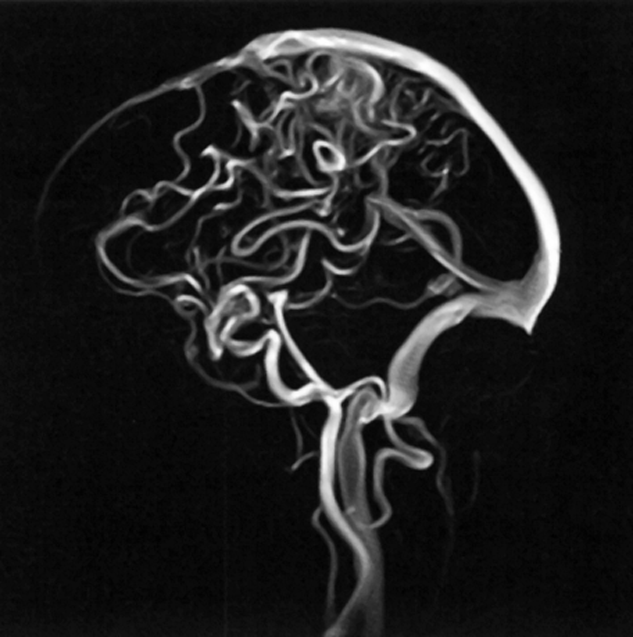

Figure 14-13:

Phase-contrast angiography.